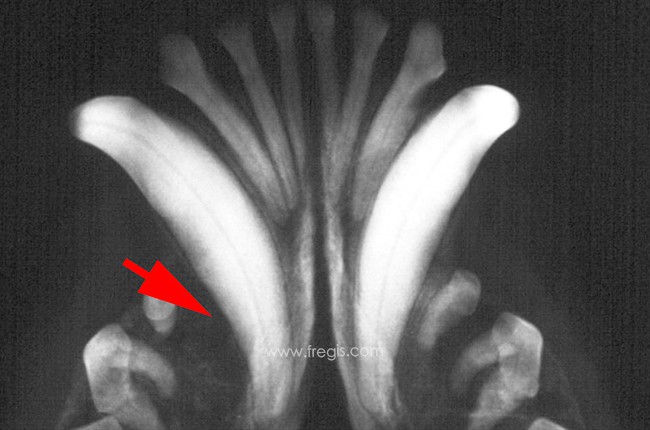

Le diagnostic de dysplasie rénale ne peut être confirmé que par biopsie rénale. La biopsie permet aussi de quantifier la gravité. Au delà de 25% de glomérules atteints, on est devant une forme grave de la maladie.

La biopsie rénale permet le diagnostic de la dysplasie rénale du chien. La flèche montre un glomérule immature et modifié (d’après Seiler et al.)Echographie des reins d’un chien atteint de dysplasie rénale